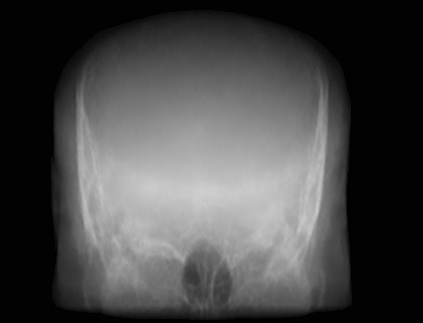

(a) Guide 𝑮𝑮\boldsymbol{G}

(b) Input 𝑰𝑰\boldsymbol{I}

(c) Guidance map 𝑴𝑴\boldsymbol{M}

(d) Prediction 𝑷𝑷\boldsymbol{P}

(e) Ground truth

(f) Guide 𝑮𝑮\boldsymbol{G}

(g) Input 𝑰𝑰\boldsymbol{I}

(h) Guidance map 𝑴𝑴\boldsymbol{M}

(i) Prediction 𝑷𝑷\boldsymbol{P}

(j) Ground truth

Figure 2: Inputs and outputs of the guided filtering pipeline based on the WDSR network. T1 & T2 MRI pairs (a)-(e) and CT & MRI projection images (f)-(j).